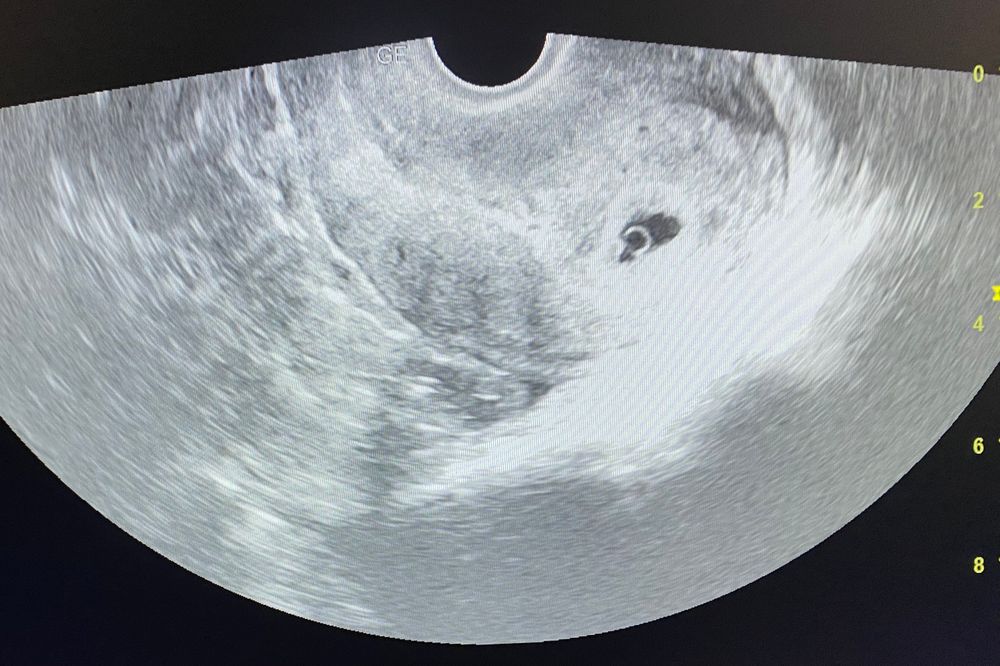

Я БЕРЕМЕННА !Вот и настал долгожданный 23 дпп Еле как дождалась Это были самые длинные 3 недели в моей жизни Сегодня прошла УЗИ И теперь я официально БЕРЕМЕННААААА

ПЯ - есть, ЖМ - есть, эмбрион - есть, КТР - 2.9, СБ +

по КТР срок 4-5 нед